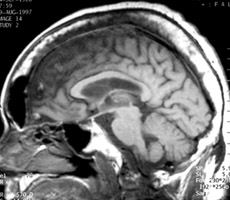

Plain film of the skull reveals a large mottled area of radiolucency with small areas of increased density within it. The MR image of the skull reveals a thickened, enlarged cranium with increase in the marrow space. Two bone scan images also reveal increased activity in the skull, more localized to one side, characteristic to the localized disease seen in Paget's. This is classic cranial involvement of Paget's. In the cranium, bone sclerosis may produce circular radiodense lesions in one area, whereas osteoporosis circumscripta is noted elsewhere. In the skull, the common region of involvement is the cranial vault. The osteolytic phase is called osteoporosis circumscripta and appears as multiple geographic, well-demarcated regions of bone resorption that may be mistaken for metastases. Focal radiodensities occur as pagetoid bone is formed. In the quiescent phase, there is a radiodense cotton-wool appearance with a thickened vault.

Lateral skull - Click on the image for a larger versionAMRI skull - Click on the image for a larger versionBBone scan skull - Click on the image for a larger versionC